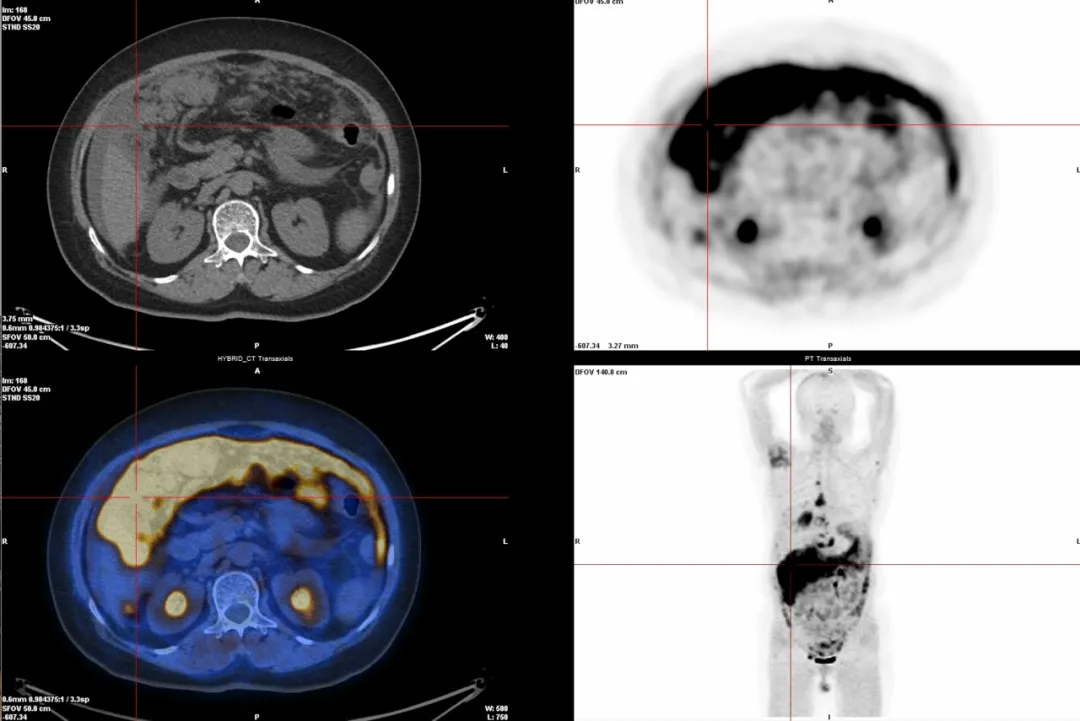

2.多种癌症检查(68Ga-FAPI):能检测很多种癌症,尤其是肝癌、胃肠印戒细胞癌、腹膜转移癌等,因为它能精准找到肿瘤周围的特殊细胞(成纤维细胞)。

△腹膜转移癌